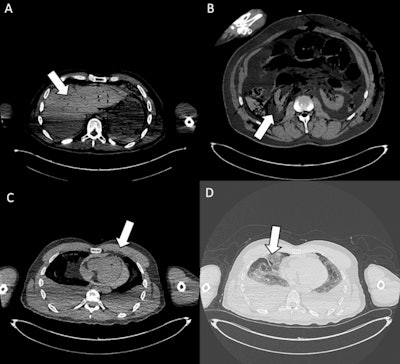

Organ injuries. (A) Axial CT scan shows traumatic injury to the bi-lobar liver parenchyma (white arrow). Moderate postmortem decomposition is also evident, with heterogeneous intraparenchymal gas distribution. (B) Cross-sectional CT image demonstrates a laceration of the right kidney (white arrow), consistent with penetrating trauma. (C) Axial CT slice shows a pericardial lesion (white arrow), with small gas bubbles in the anterior pericardial region, indicative of traumatic pericardial injury. (D) CT image highlights a laceration of the right middle lobe (white arrow), associated with pulmonary contusion, omolateral pneumothorax, and bilateral pleural effusion. In the assessment of organ injuries, inter-reader agreement was only moderate (Fleiss’ kappa = 0.52). Sensitivity was again limited among less forensic-experienced readers (31% and 51.7%), reflecting the interpretative complexity and reduced diagnostic accuracy of postmortem CT in this setting.